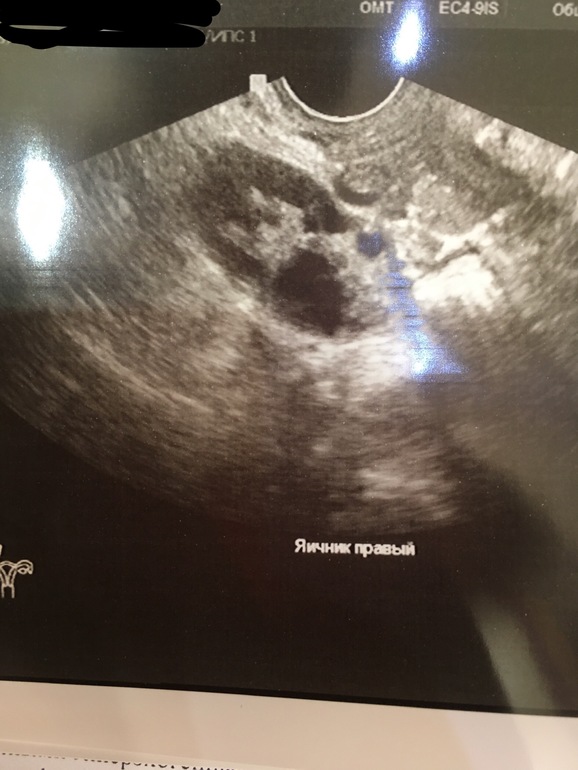

Узи, ничего не поняла 😂

УЗИ, Фолликулометрия

Была овуляция или нет

Девчонки, помогите!!!!! Сделала УЗИ... Большой доминантный фолликул